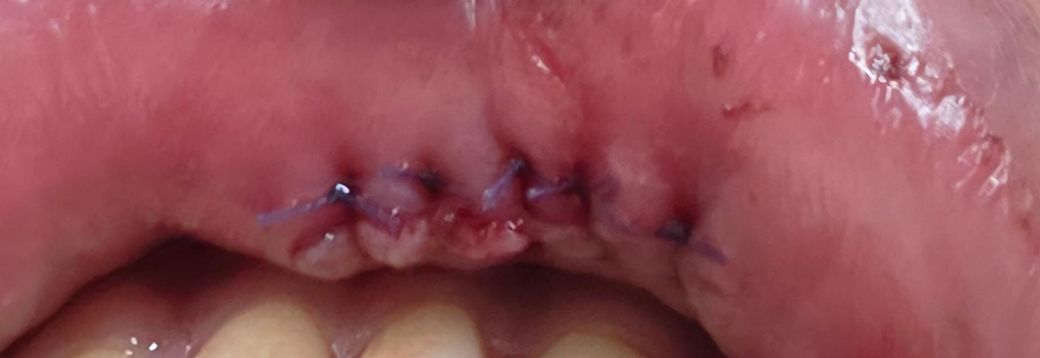

입술, 입안 봉합수술 관리(상처 부위 사진 있음)

(14일)에 아랫입술 9바늘, 입술 안쪽 5바늘 봉합하고